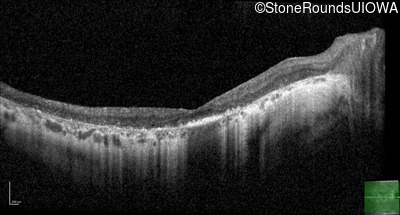

Optical Coherence Tomography - Left - 20/70 +1

Exemplar / OCT Stack